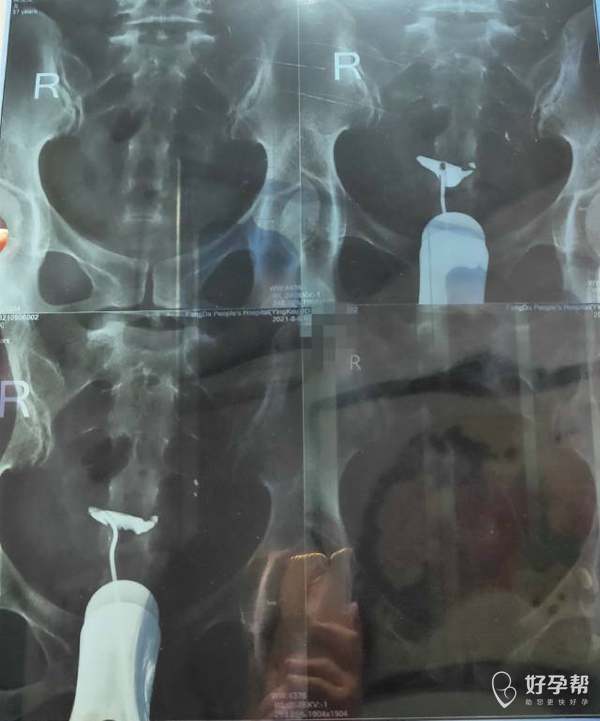

输卵管造影双侧不通,可以做试管,如果非常想自己试孕,要做宫腹腔镜检查,继续导丝疏通输卵管,如通畅了马上卵泡监测指导受孕。

37周岁,这种情况好治疗吗?怎么治疗方法好呢?